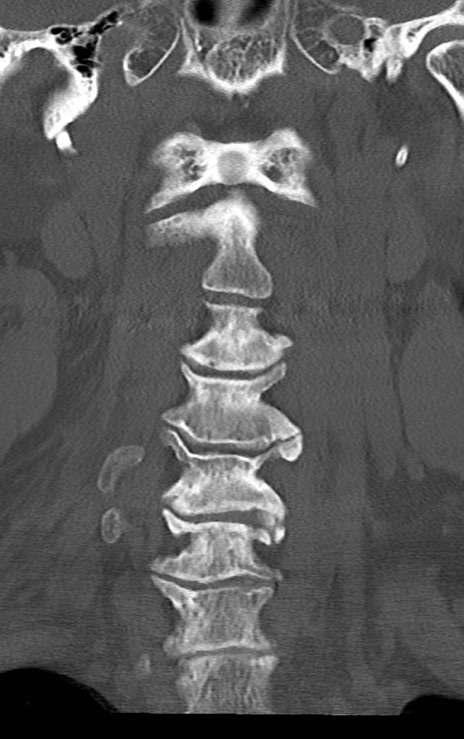

頚椎CT

矢状断像